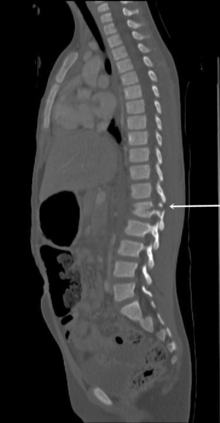

Many children with spinal cord injury have ligamentous injury with no evidence of vertebral fracture or other radiographic abnormalities on routine (anteroposterior and lateral) spine radiographs or CT scan.42a These children have spinal cord injury without radiographic abnormality (SCIWORA), and many of these patients develop permanent neurologic injury.3,23

Nurses should carefully assess movement and sensation in all extremities on admission and at frequent intervals throughout the child’s hospitalization (see Chapter 11). The mechanism of injury should increase the index of suspicion of spinal cord injury. For example, a child wearing a lap belt without a shoulder strap who presents with abrasions or contusions on the lower abdomen may have an acute flexion injury of the lower spine (with or without a Chance fracture).